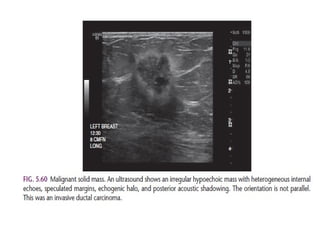

Spiculated with radiating lines from the mass is a very suspicious finding.

The density of a mass is related to the expected

attenuation of an equal volume of fibroglandular tissue.

High density is associated with malignancy.

Here a hyperdense mass with an irregular shape and a spiculated margin.

Notice the focal skin retraction.

This was reported as BI-RADS 5 and proved to be an invasive ductal

carcinoma.